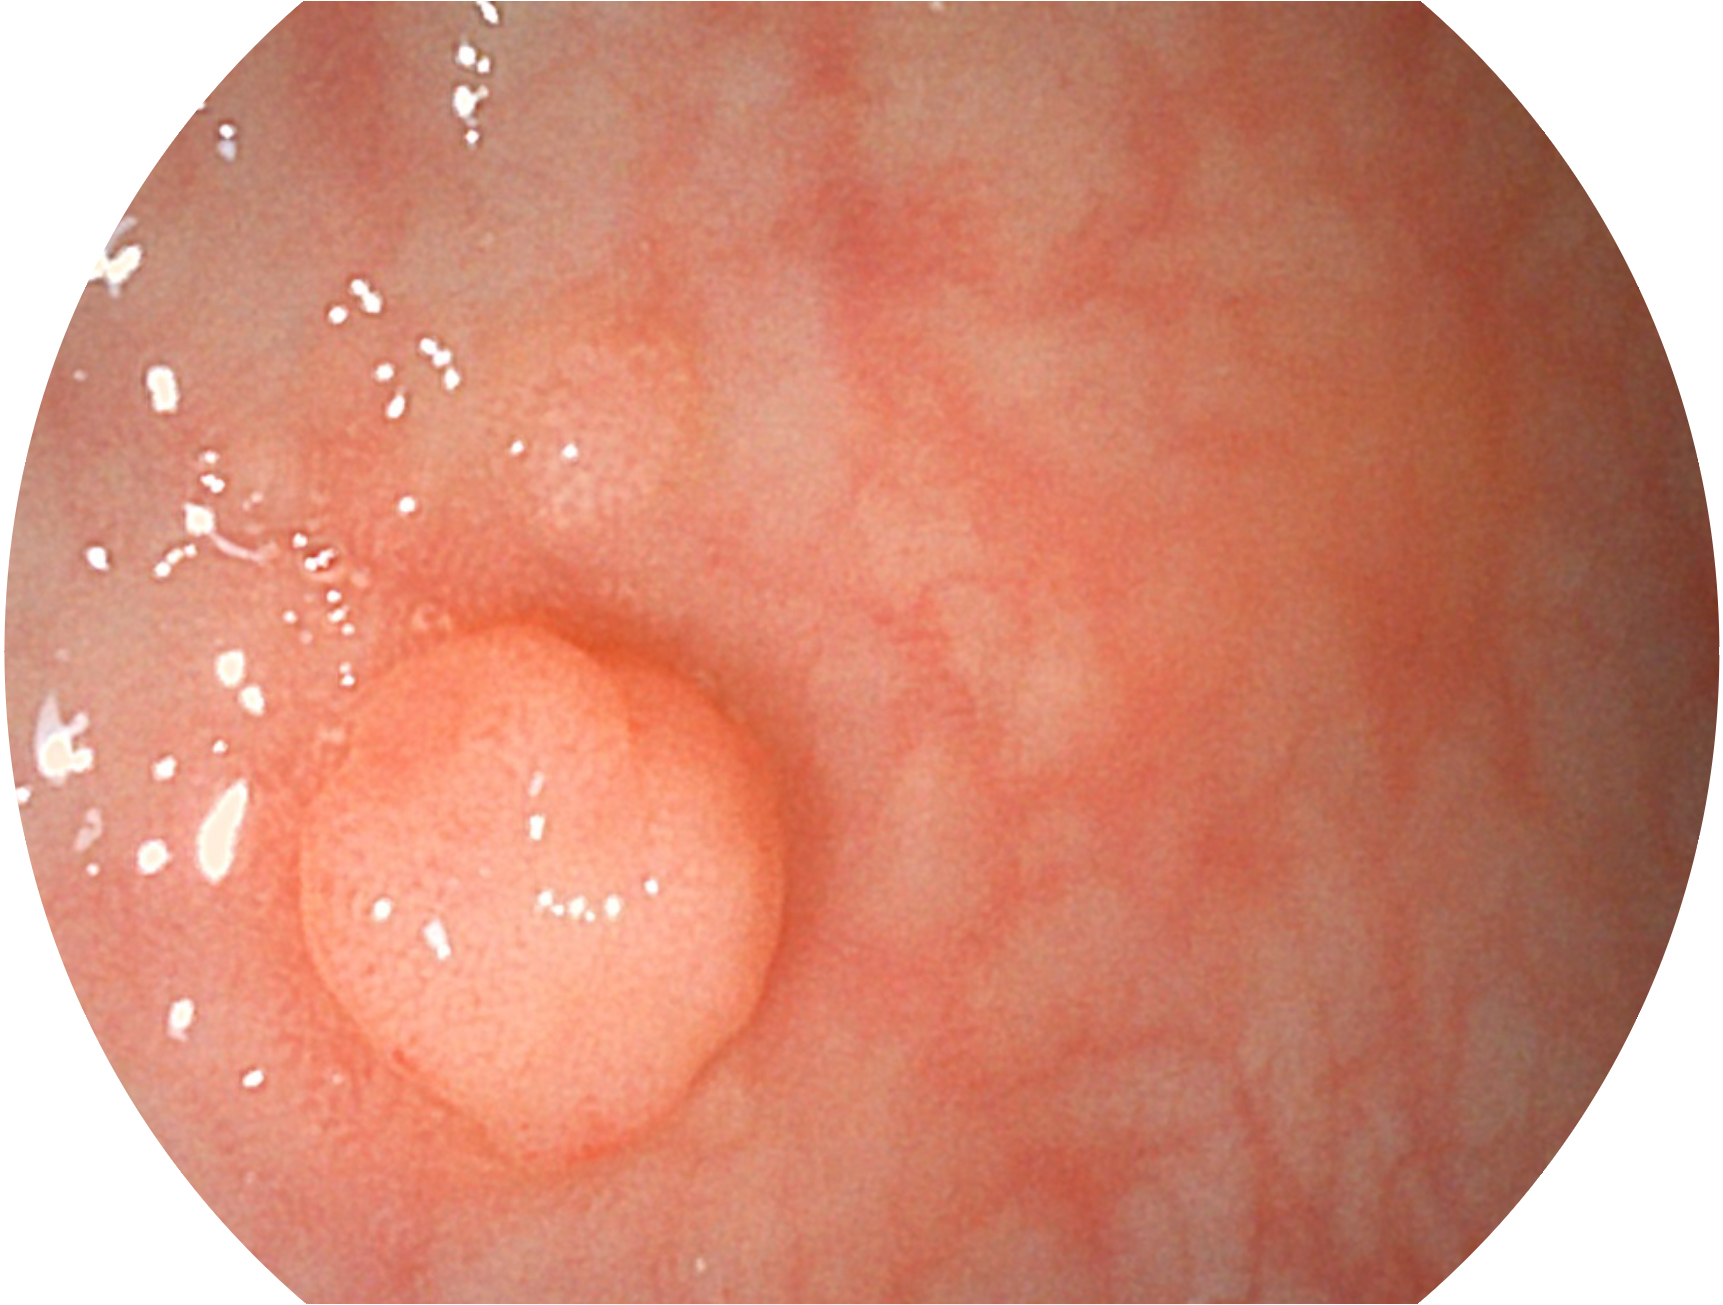

与上一代VIST相比,摒弃了滤光转轮而直接采用光谱组合的方案,加入了血红蛋白吸收高峰与次高峰的蓝紫光和绿光光谱,更有利于黏膜血管吸收,突显浅表层血管和中层血管的对比度,因而具备更高的图像对比度,近景观察时,有助于微细结构变化及病灶边界的观察。

• 白光图像 VIST图像